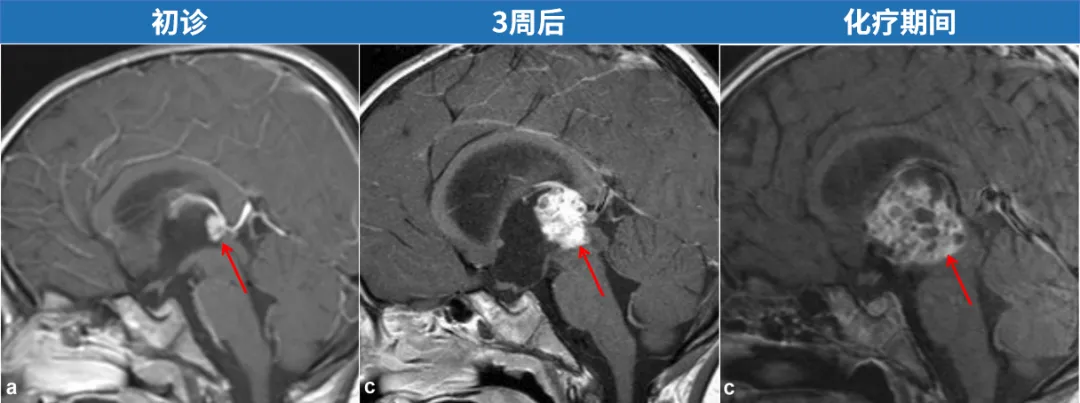

10天后,KK情况并未好转,他再次因剧烈头痛和呕吐入院,但这次并未进行影像学检查,医生仅为孩子进行腰椎穿刺以排除脑膜炎,随后出院。没想到,短短8天后,KK的症状急剧恶化,这一次的核磁令全家人震惊不已,当初那个不起眼的小白点竟疯狂长大,变成了几乎要夺走孩子生命的“恶魔”——已造成导水管梗阻和脑积水。

由于内镜手术只是解决了脑积水问题,但那个可怕的肿瘤依然存在,始终威胁着KK的小生命。为此,医生立刻启动两个疗程的化疗,“但我们在化疗期间发现,患儿的肿瘤一直在生长,并逐渐阻塞双侧室间孔,我们讨论决定只能进行脑室腹腔分流术,这是当时挽救患儿生命的唯一方法。”

更令家属绝望的是,在随后的2个月里,即使KK经历了大剂量化疗和干细胞移植,但肿瘤仍在增大。